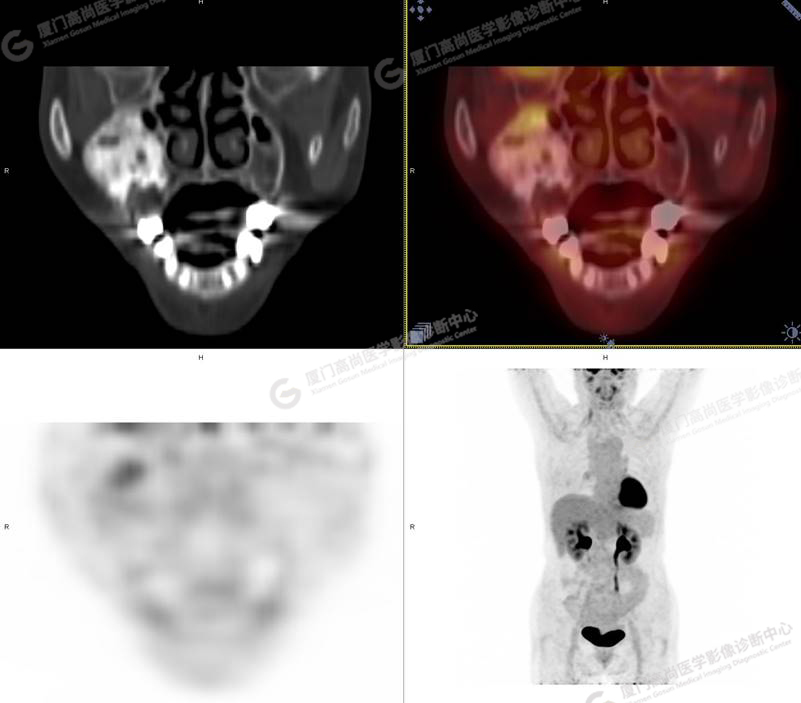

圖1

圖4

PET/CT所見:右側(cè)上頜骨、右側(cè)顴骨及右側(cè)額骨骨質(zhì)膨脹,其內(nèi)密度不均勻性增高,部分放射性攝取輕微增高,SUVmax 2.27。